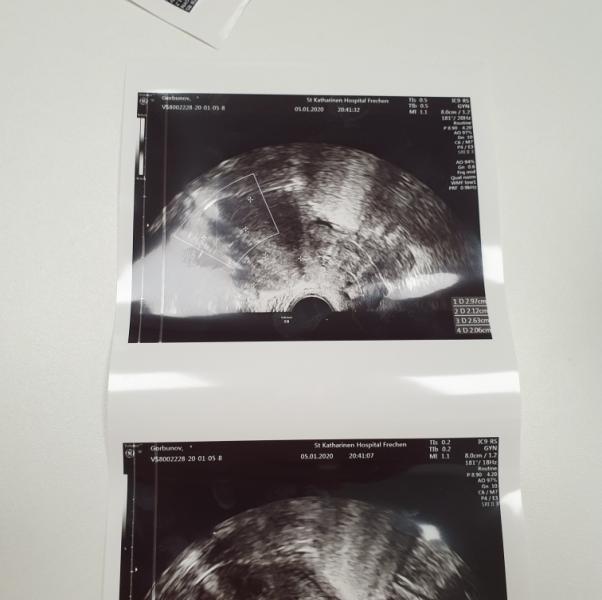

Девчата приветствую всех 🖐 давненько здесь не была! Я к вам обращаюсь с вопросом, за советом! У меня месячные начались с 16 декабря и по сей день продолжаются! Первую неделю просто мазало, как в первый день месячных, после 2 недели то обильно , то средне , как в обычные дни....затем начали сопровождаться с болью, ноющие , тянущие боли, а последние дни очень сильно болит матка , до такой степени как на посл. мес. Беременности, я не могу спокойно обуть обувь либо игрушки собрать с пола..... такое ощущение как будто в внутри большой ребёнок, давит и болит......сегодня ездили в госпиталь, не дождавшись утра, т.к. страшно стало, такое ощущение , что лопнет матка😫 Вчера ещё хотела написать и спросить у кого так было, но не стала, полезла в инет , прочитала симптомы.....и совпало! Мне сделали внутреннее УЗИ, обнаружили 2 опухоли миомы. Я не была у гинеколога около 4 лет. Размер не значительный, первая чуть больше 3 см. Вторая 2 см с лишним. Врач сказал оперировать в месте с маткой, т.е.всё удалят, т.к. эти опухоли не возможно убрать потому что они не с краю. И у меня сразу шок! Ведь я хочу ещё родить ребёночка!😥 Второй вариант пить медикаменты, опухоль может стать меньше, но....тяжело вынашивать ребёнка , т.к. могут быть осложнения, постоянно кровоточить, то мало , то обильно! У меня вопрос к вам девчули: может кто то сталкивался с такой проблемой, либо ваши близкие, подскажите как лучше поступить! Всем спасибо заранее !❤